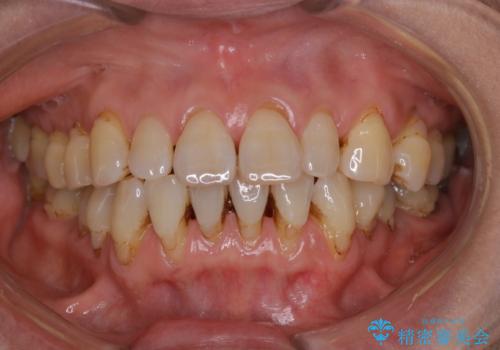

- クリーニングがかなり久しぶりで、全体的にきれいにして欲しいとのことで来院されました。全体的にステインの量がとても多かったため、施術前にご相談をし、60分コースでできる限りのステイン落としを行うこととなりました。今回は審美的に見える表側をメインでPMTCを行いました。

毎日丁寧に歯磨きをしていても、日常生活での飲食物などにより着色してしまうことはあります。PMTCでは、歯の表面の凸凹にミネラルを補給して、ツルツルの表面に仕上げます。定期的にPMTCを行うことにより、歯質の強化になり着色がつきにくい状態になります。